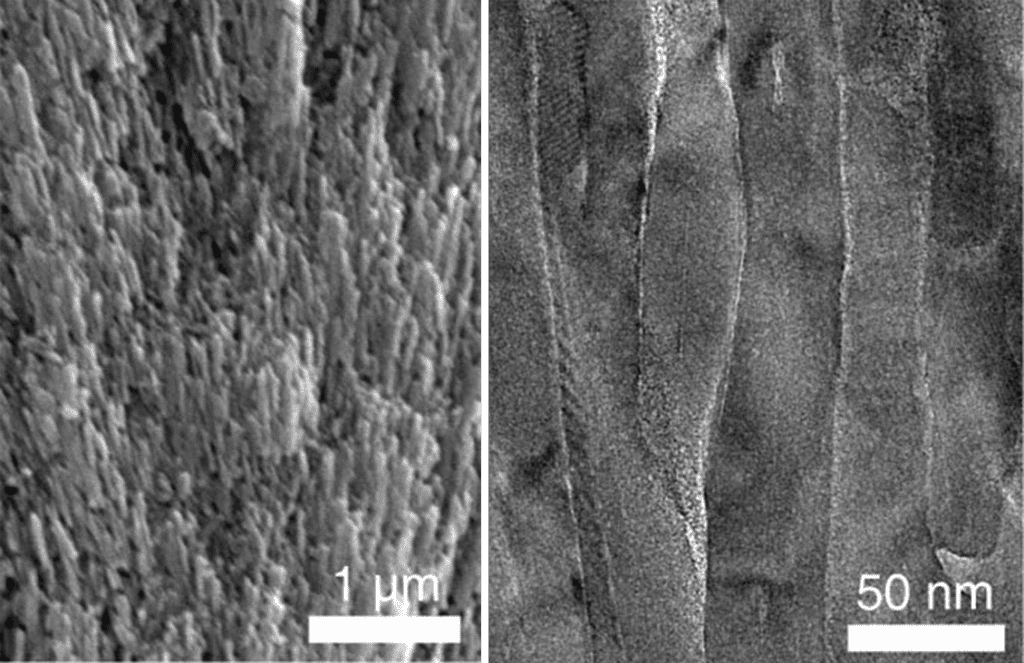

يأتي جزء من قوة المينا، وسبب صعوبة تركيبه، من بنيته المعقدة والدقيقة. هذا الدرع الممعدن مصنوع من أنابيب صغيرة مترابطة تعرف باسم «العصي النانوية»، والتي تكون مليئة بشبكة من «هيدروكسيباتيت الكالسيوم»، وهو نوع من معدن فوسفات الكالسيوم. تقول موراديان-أولداك: «البلورات هي التي تجعل مينا الأسنان فريداً جداً».

وفقاً لموراديان-أولداك، تتجمّع هذه البلورات النانوية معاً على شكل منشور، وتكون كلها مرتبطة ببعضها. تقول موراديان-أولداك: «إنها مثل السباغيتي الجافة قبل أن تُطهى». لكن بنى العصي النانوية البلورية الصلبة يمكن أن تنكسر دون وجود بطانة داعمة. عندما تضغط قوى المضغ على هذه العصي، تمتص طبقة غير متبلورة مكونة من المغنيزيوم والبروتينات ومركبات أخرى القوى والضغط حتى لا تنكسر العصي.

تقول موراديان-أولداك: «تكون كل من هذه العصي النانوية الصغيرة مغطاة بمادة غير متبلورة»، وتضيف: «المواد المرنة هي لينة، والمواد الصلبة هشة، ولكن ما يفعله المينا حقاً هو الجمع بين الاثنين». يقول كوتوف إن المرونة الطفيفة للمواد غير المتبلورة هي عنصر أساسي في التنظيم البنيوي الذي يعطي مينا الأسنان قوته الميكانيكية.

وفقاً لزاو، لتركيب مينا الأسنان الاصطناعي، صنع المهندسون عصي الهيدروكسيباتيت النانوية البلورية المرتّبة بدقة، وطلوها بثاني أوكسيد الزركونيوم، وهو نسخة أقوى من مادة المغنيزيوم غير المتبلورة. يقول كوتوف إن هذا الضبط والتعديل للبطانة جعل المينا الاصطناعي «مكافئاً أو أفضل» من المينا الطبيعي. يقول كوتوف: «كانت الدراسات السابقة قادرة على محاكاة المينا بعصي نانوية متبلورة بالكامل، والتي يتصف أداؤها بالجودة إلى حد معقول ... ولكن ليس بنفس الجودة التي حصل عليها [فريقنا] عندما أضاف طبقة المواد غير المتبلورة. تُظهر هذه الدراسة بطريقة جميلة وبشكل مقنع للغاية أنه يمكن تصنيع نسخ أكبر من هذه المواد عالية الأداء».